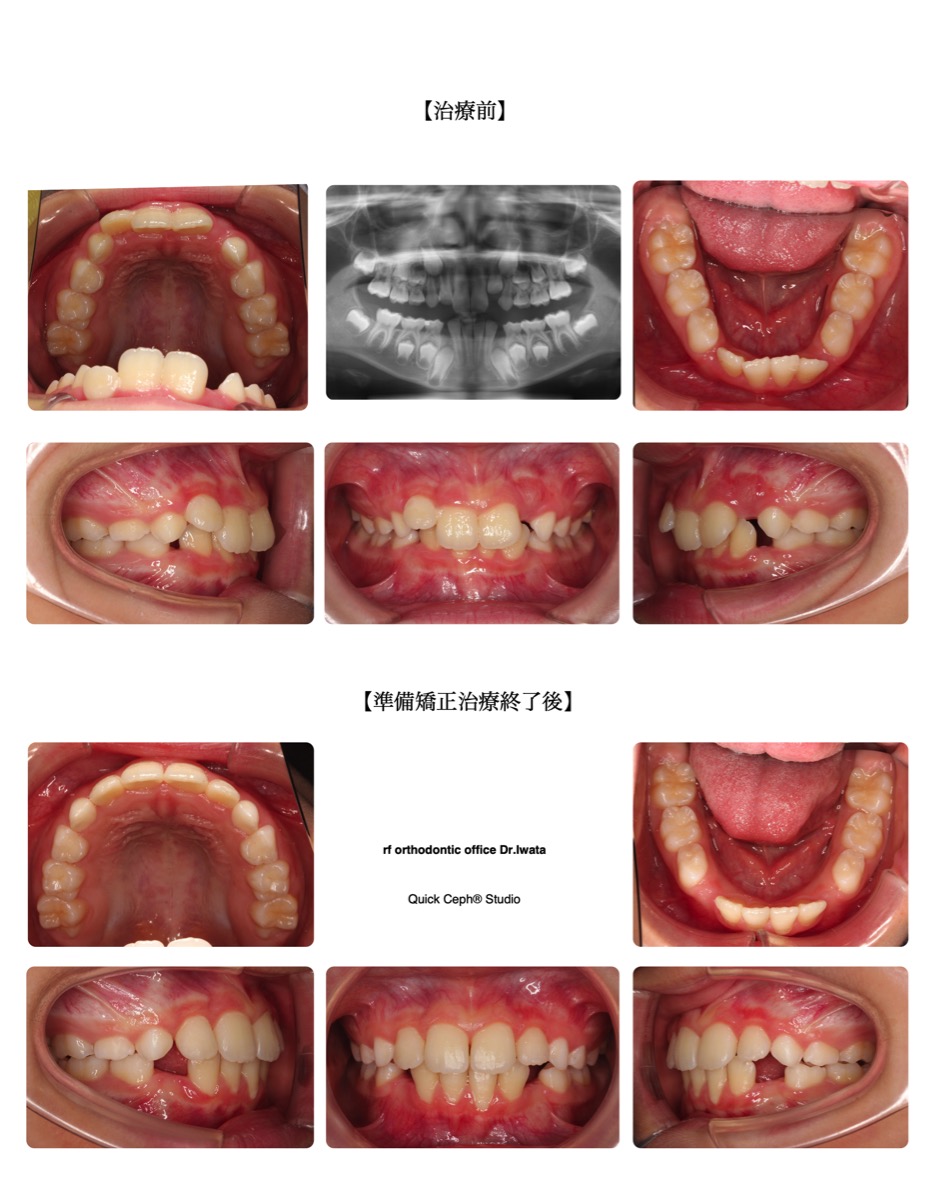

叢生症例 <前突を伴う叢生に対する準備矯正治療>

【主訴】上下の前歯デコボコして生えてきた。前歯でものが食べづらく口も閉じにくいため矯正で綺麗にしたい。【主な…